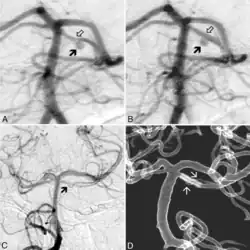

Aneurismas

Los aneurismas pueden tratarse con técnicas endovasculares novedosas como el sole stenting,[5] aunque ha sido objeto de controversia con otros autores.[6]